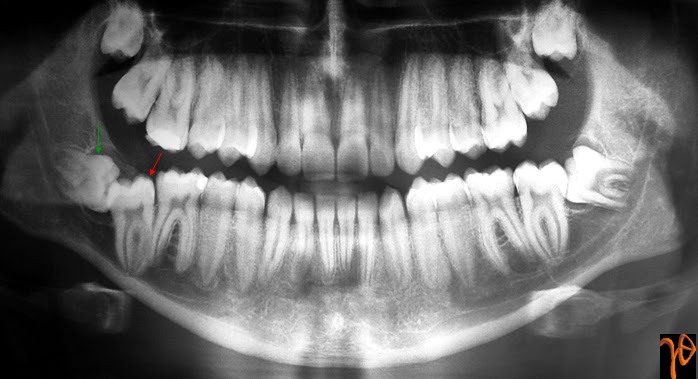

Εικόνα 1. Πανοραμική ακτινογραφία στην οποία αποκαλύπτονται οι έγκλειστοι #47 (κόκκινο βέλος) και #48 (πράσινο βέλος).

SUMMARY. This post presents a clinical case of a 18-year-old male patient presented with an unerupted mandibular second molar. A follicular cyst was associated with the crown of the neighboring impacted wisdom tooth.